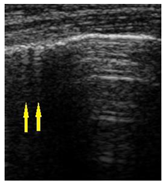

| LUS Score | 0 Points | 1 Point | 2 Points | 3 Points |

|---|---|---|---|---|

| Image |  |  |  |  |

| Description of image | Normal or physiological pattern displaying A-lines (right part), along with two sparse B-lines (yellow arrows) per intercostal space | Three sparse B-lines (yellow arrows) per intercostal space, accompanied by pleural abnormalities, such as irregularities or thickening (orange circle) | Small peripheral consolidations smaller than 1 cm (red dotted area), a small area with ‘white-lung’ appearance, adjacent coalescent or merging B-lines | Substantial peripheral consolidations (marked with red) wider than 1 cm with the presence of air bronchograms (hyperechoic areas inside); the image is from an infant with bacterial pneumonia not included in this study |